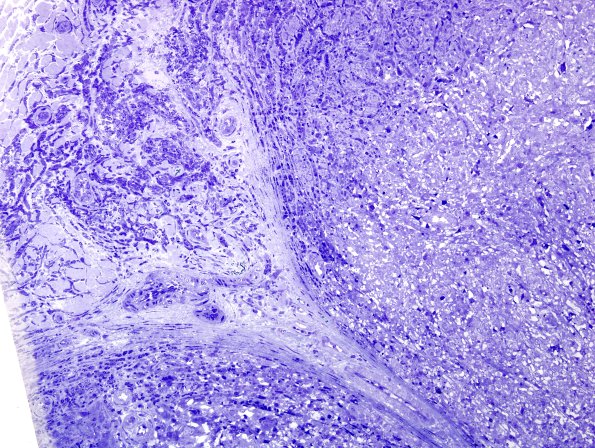

2A4 Leprosy, lepromatous (Case 2) Plastic 5

2A4,5 The growth pattern in this area appears reticulated. (plastic sections)